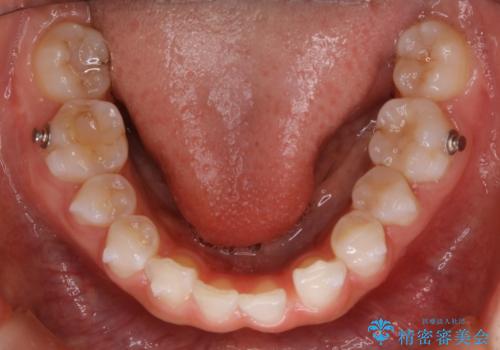

ガタつきがあるだけでなく、元々永久歯が欠損している「先天欠如」で歯の本数が少なく噛み合わせ等も治療する必要がありました。

かなり特殊な状況からの矯正治療になるため抜歯する本数や位置、並んだあとのスペースのコントロールを慎重に計画し、マウスピース装置のインビザラインで治療を開始しました。

稀に、乳歯が抜けてもその後に永久歯が生えてこないことがあります。生まれつき歯の元となる「歯胚」というものが欠如していることが原因で本数が少なることを「先天欠如」といいます。

こういったケースの治療では欠損している歯の本数分反対の顎の歯(上顎に欠損がある場合は下顎の歯)を抜歯してスペースの調整をする場合や、欠損歯の幅分のIPRを反対の顎の歯に設定することでスペースのコントロールをするという方法、欠損している歯の分のスペースを残して矯正を終了し最後にブリッジ治療やインプラントで歯の本数を増やすという方法があり、状況や患者さんの希望により選択をしていきます。